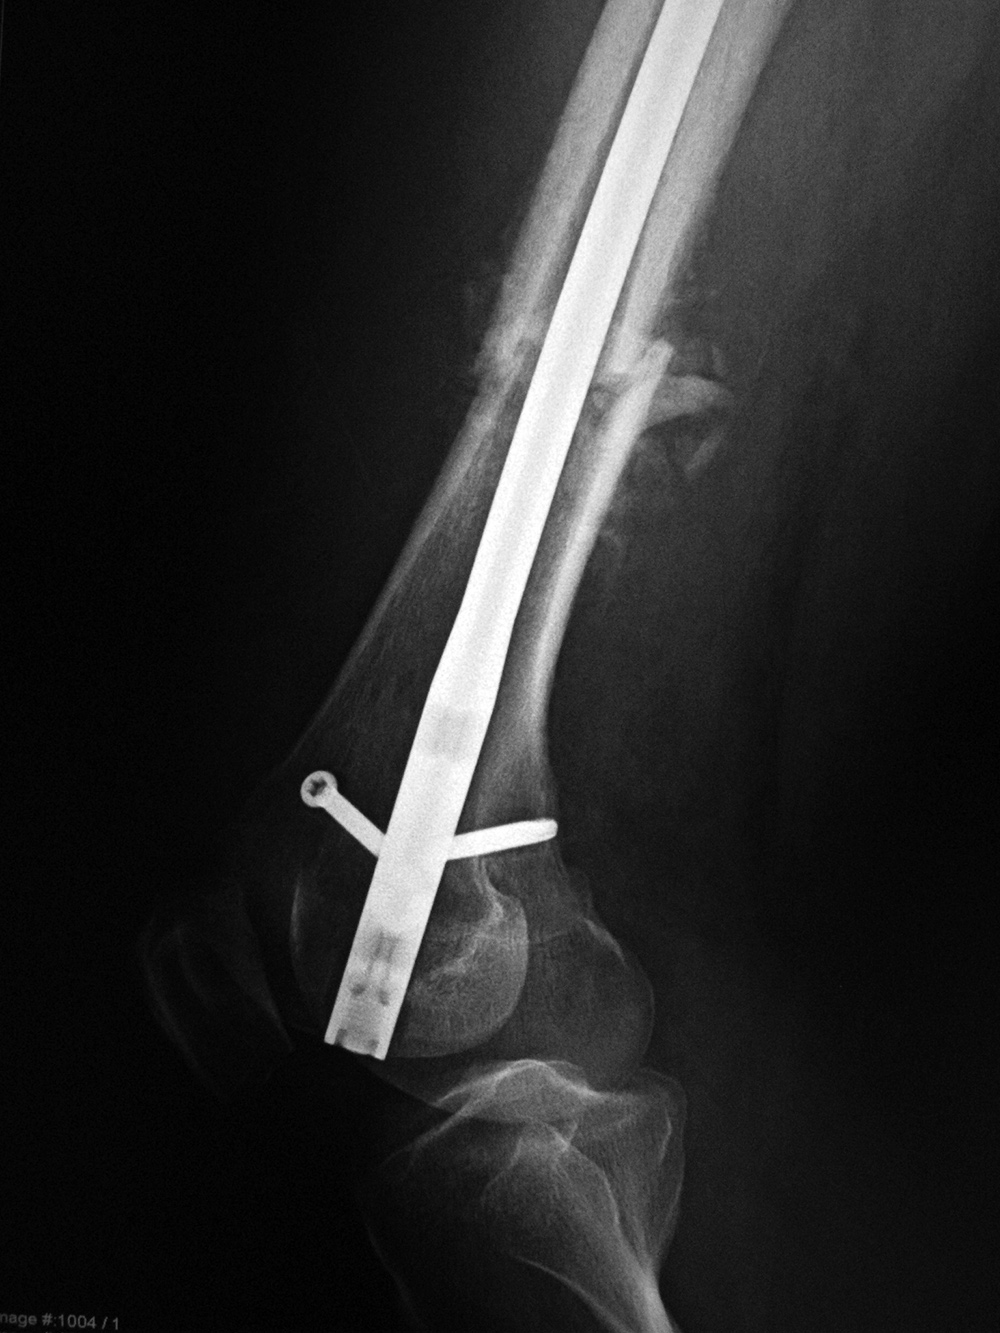

| Failure of fracture fixation due to ambulating against advice |

| Male patient with proximal tibia and fibula fractures treated by intramedullary nail and supplemental one-third tubular plate. Initial intraoperative fluoroscopic AP and lateral images (left two images) show the plate (arrow on lateral image). The patient ambulated against advice and was lost to follow-up. Two months later he again presented (right two images) to the clinic. There is now tibia fracture migration, and the proximal medial to lateral interlocking screw has backed out (AP view). The lateral view demonstrates fracture displacement with flexion deformity. The nail has troughed outside the proximal anterior tibia and is sitting within the soft tissues. The supplementary plate is broken, there is a broken interlocking screw, and abundant fracture callus is present. |